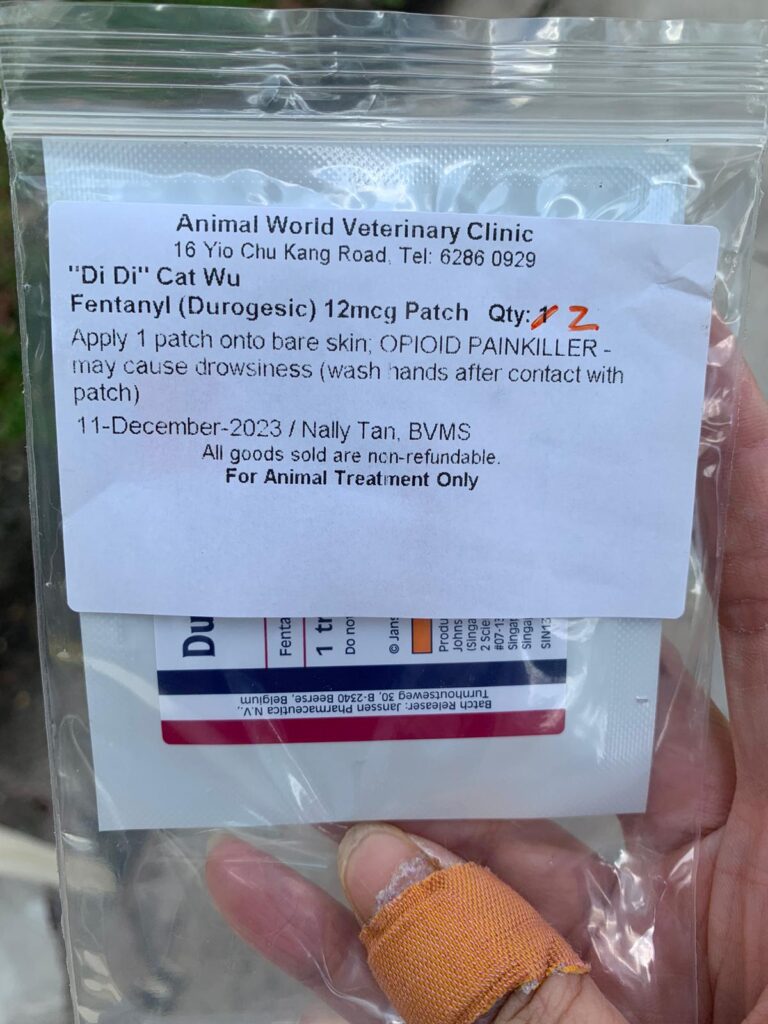

Night: Tmr got to put new f patch for him or give bupre alr

10am: eyes more discharge I assume is due to pain, today will shave his ear and put f patch and give bupre and Subcut

Night; did looks more in pain. Bupre in the day not enough. Have to put f patch

Morning: looks in pain. Give Subcut and bupre. I don’t have f patch in 5G. scanned on 19.4.24 no m/c.

Morning: got helper in to cut nails, steam bath and clean ears. She can handle him alone. Given Subcut bupre n put on f patch for him.

Morning: got 2 helpers in to clean up and for him: cut nails, clean ears and steam brush fur. His f patch if off, given Subcut and bupre jab

Morning; both eyes discharge look bad, clean up and put banocin on his ear. Will Subcut him and give Clav jab and bupre n put on new f patch for him

Morning: Subcut n on regular med and place new f patch n still given bupre

Morning: just logging down that past days he isn’t on any painkiller cos bupre no more. Tmr morning will put on a f patch and give him bupre also

10am+: b4 I Subcut n give painkiller still eating ok. Subcut and given b12 b com bupre and put on a f patch (end 1.3.24)

11Am+: given bupre jab and place a f patch on his left ear.

Morning: his fentalyn is off. Given Subcut and bupre.

Morning: didi constipated, saw him in 2 bins, trying to squeeze out something n can’t n he try to rub on floor – aren’t that pushing that piece in? I help him push out the 2cm piece 5/10, and he go to bin 03 and poo out another 12cm. So is that piece stuck n he is so uncomfortable. Subcut him w bupre also. His f patch still on. Can tear off soon. Need to buy more

Morning: will meow. Like to eat Sanyo pink elderly food. His f patch still on it

Just status update: Today Subcut n given b12 b com also. Given bupre and fercosang also. eye more discharge. Pain. Shave his ear and place a f patch also.

Night; mmm”Don’t look good.”- pic is in pain. Tmr got to try a f patch on him again

His f patch is off alr

1+pm back to 猫房 w f patch. Clean his ears and only manage to cut off some of his ears fur w scissor. I don’t have shaver for 5G have to go buy. Sigh. Put a patch on his right ear. Still v responsive to me sayang and head butt

I need to measure his weight and change to higher dose for him. I think I need to put a f patch for him